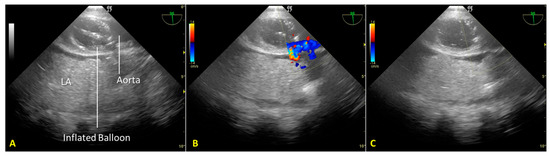

Cardiac arrest occurred rapidly with the cessation of life support. After checking the asystole on continuous ECG monitoring for twenty minutes (“no-touch period”), we certified the patient’s death. We performed post-mortem percutaneous femoral cannulation using the previously placed introducer wires. A 19 Fr cannula was placed in the right femoral vein (draining cannula) and a 17 Fr cannula in the right femoral artery (reinfusion cannula). Before starting the A-NRP, we inflated the AB according to the manufacturer’s instructions, which—considering the thoracic aorta diameter of 30 mm, as measured from a recent CT exam—was with 19 mL of saline (Figure 2A). We set extracorporeal blood flow to be greater than 2.4 L/min/m2, corresponding to half of the patient’s body surface area.

Nevertheless, abdominal aortic regional pressure remained consistently suboptimal (approximately 45 mmHg) [12]. A transesophageal color Doppler echocardiography scan to obtain a mid-esophageal descending aortic long-axis view demonstrated incomplete occlusion of the thoracic aorta (Figure 2B). Due to atheromatous plaques, the incomplete aortic occlusion required an additional 15 mL of saline. Real-time US-guided insufflation made filling the aortic balloon (AB) possible. AB is just enough to achieve total aortic occlusion but not so much as to risk balloon hyperinflation, which could cause aortic rupture, balloon rupture, and abdominal AB extension with celiac trunk occlusion (Figure 2C).

Figure 2. (A). Mid-esophageal descending aortic long-axis view scan: the endovascular occluder (RELIANT® catheter balloon, Tamworth, UK) is visible in the descending thoracic aorta. (B). Incomplete occlusion of the thoracic aorta during the initial phase of regional extracorporeal support for organ retrieval. Transesophageal color Doppler echocardiography documents the passage of blood around the aortic occluder. (C). Complete occlusion of the thoracic aorta after additional filling of the RELIANT® AB. Absence of blood flow in the thoracic aorta above the occluder. LA—lung atelectasis.